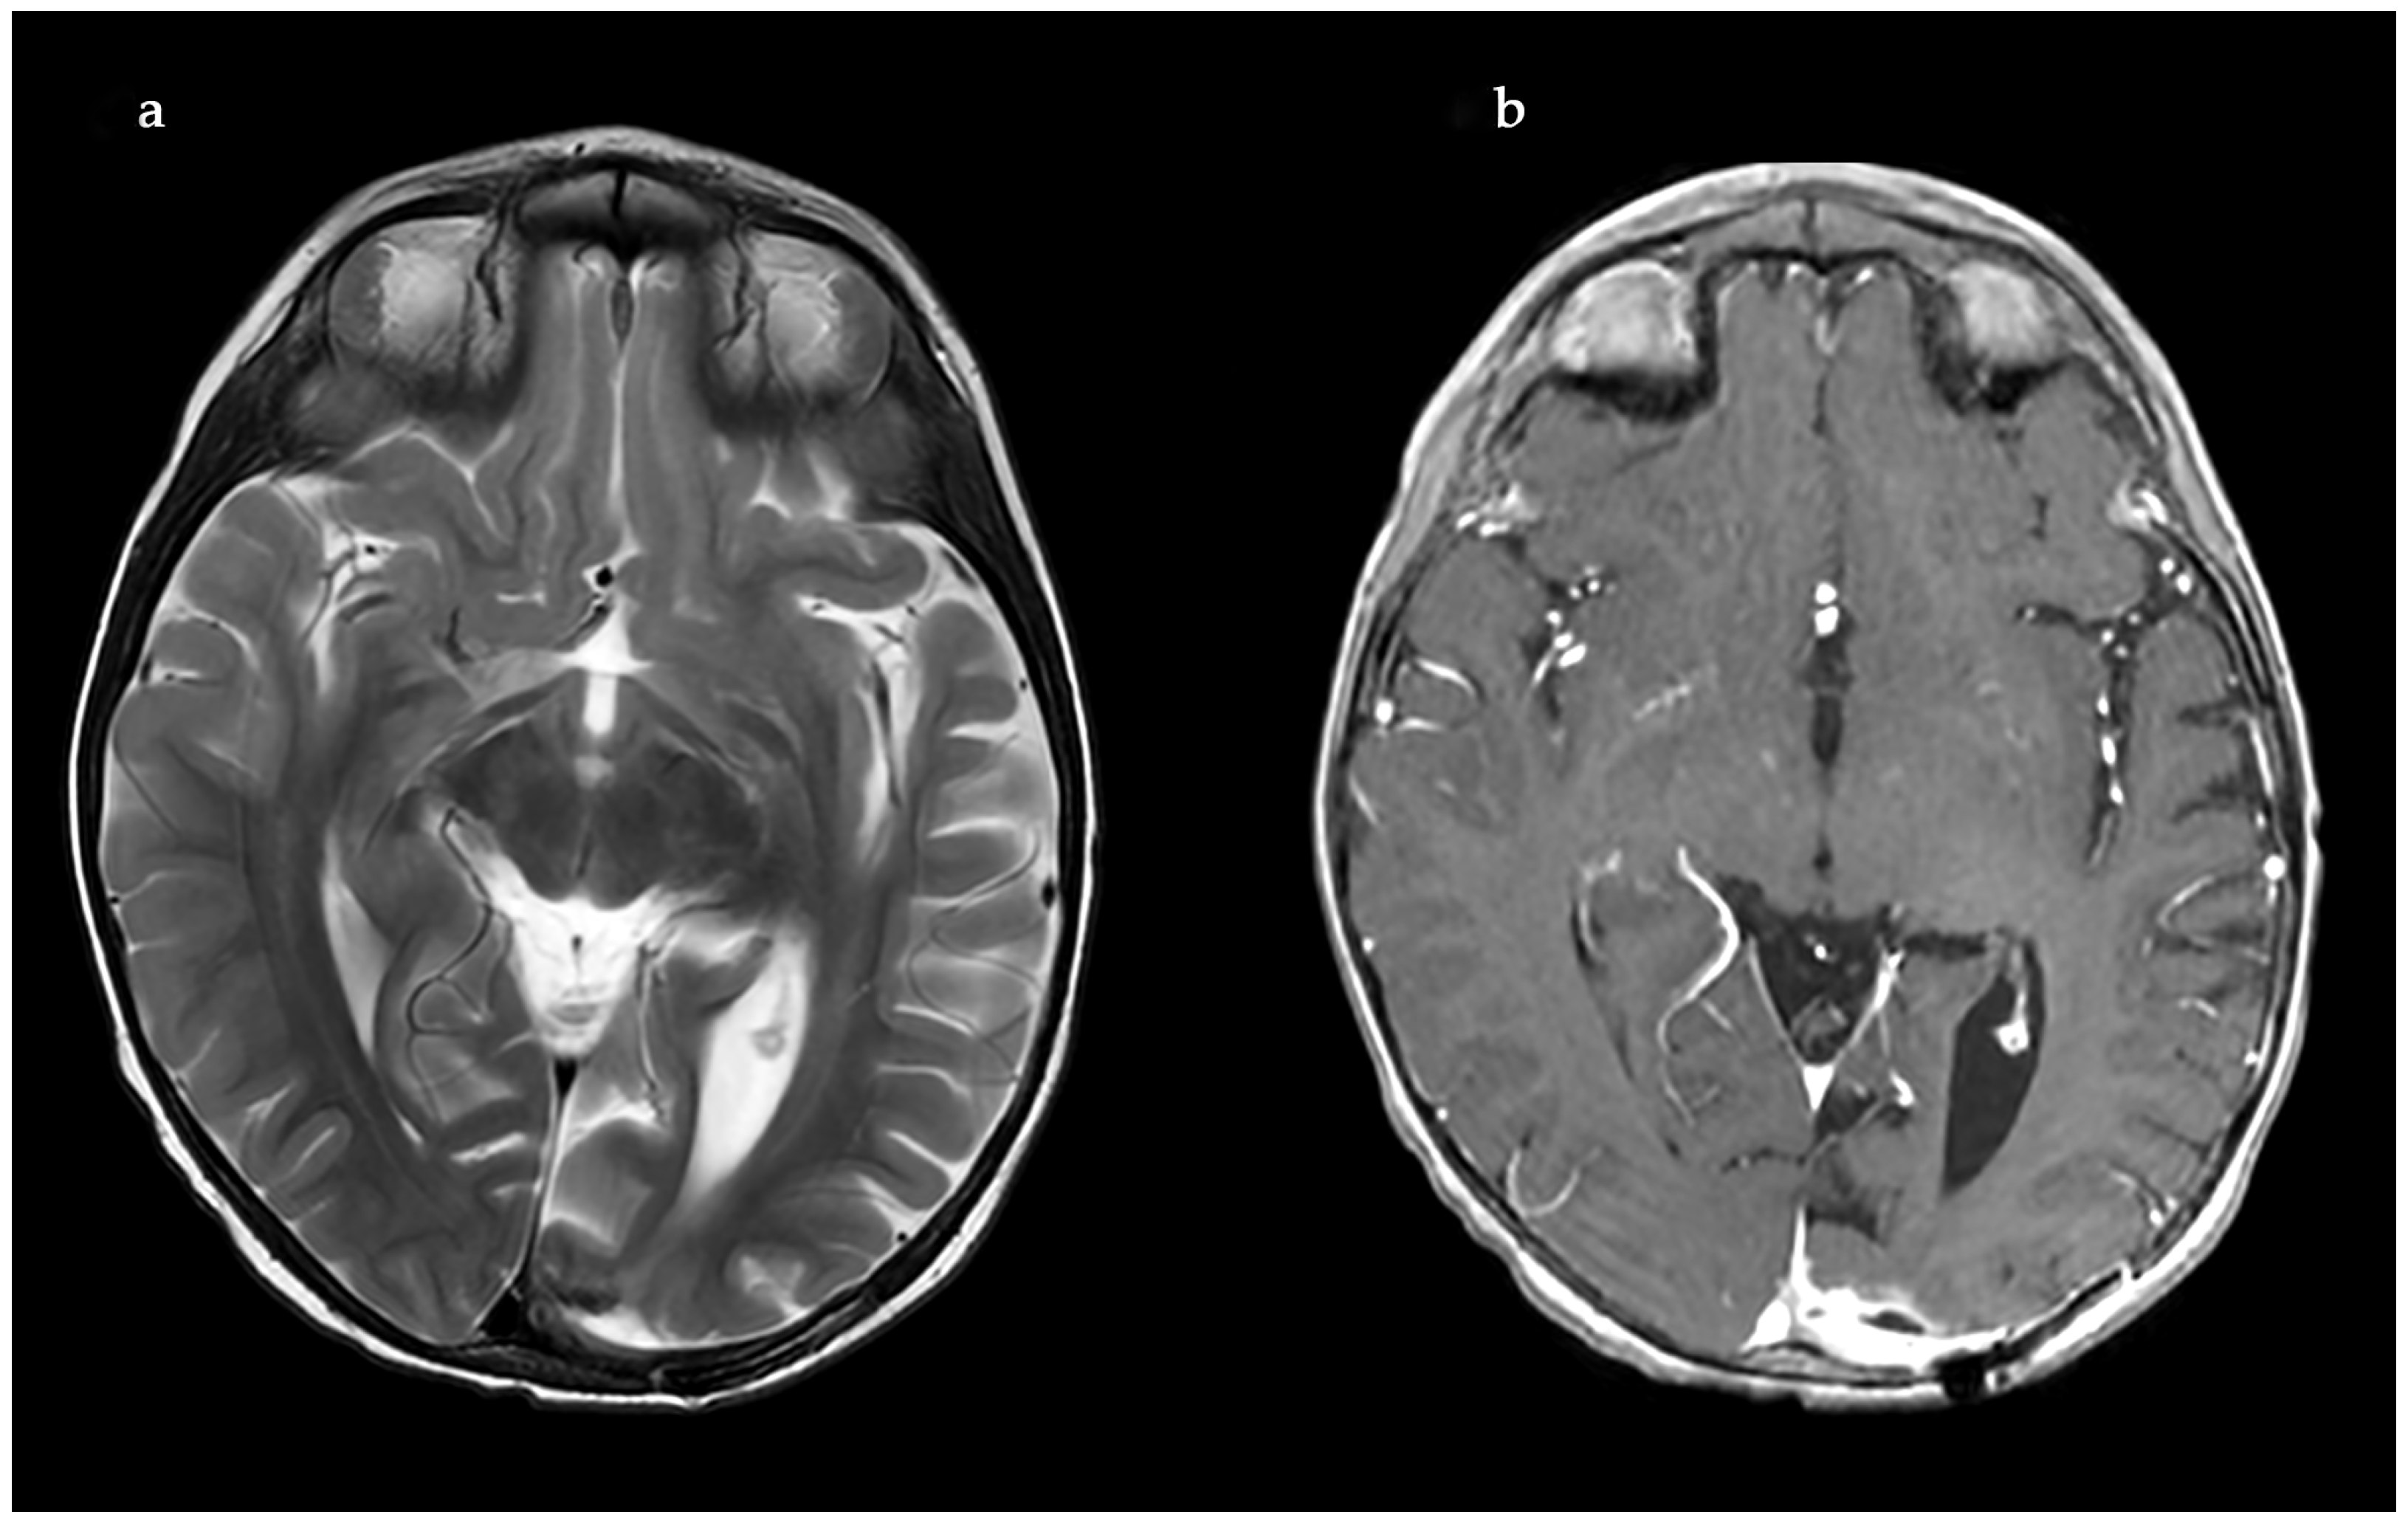

2. Case Report